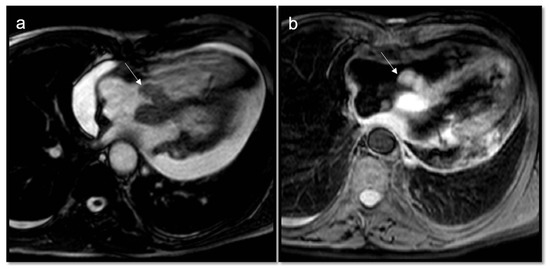

- Malignant masses often show heterogeneous enhancement; typically, angiosarcoma shows early avid enhancement as it is richly vascularized.

- Trombi due to their avascular nature appear non-enhanced.